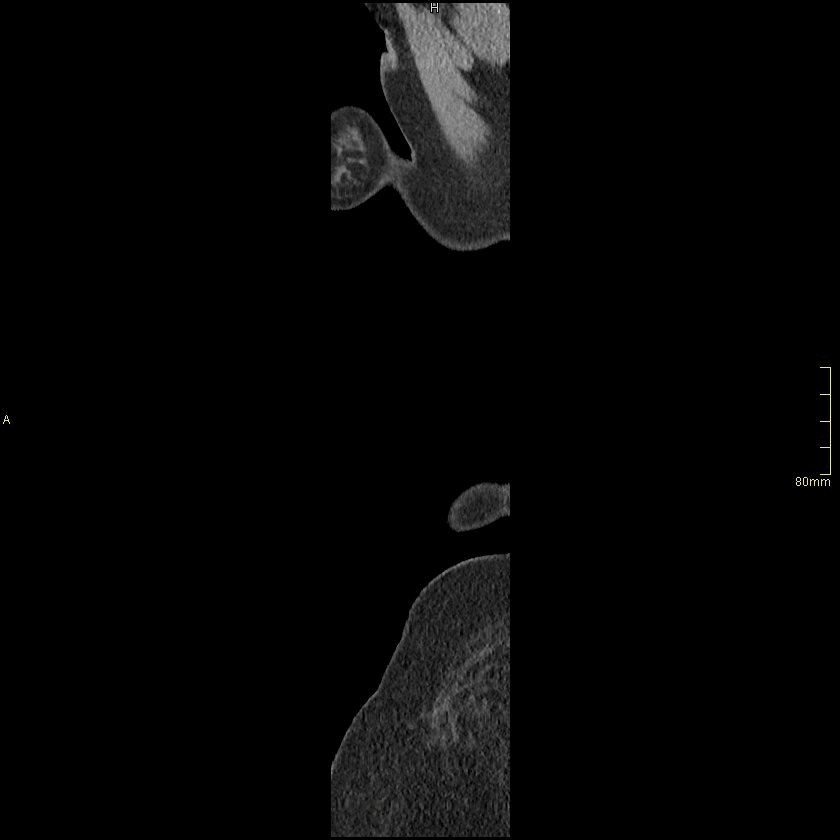

Example below is a General Chest/Abdo/Pelvis without contrast. Bony reconstructions are available depending on clinical question and differential diagnosis

Chest/Abdo/Pelvis (Coronal)

Lung (Coronal)

Chest/Abdo/Pelvis (Sagittal)

Lung (Sagittal)